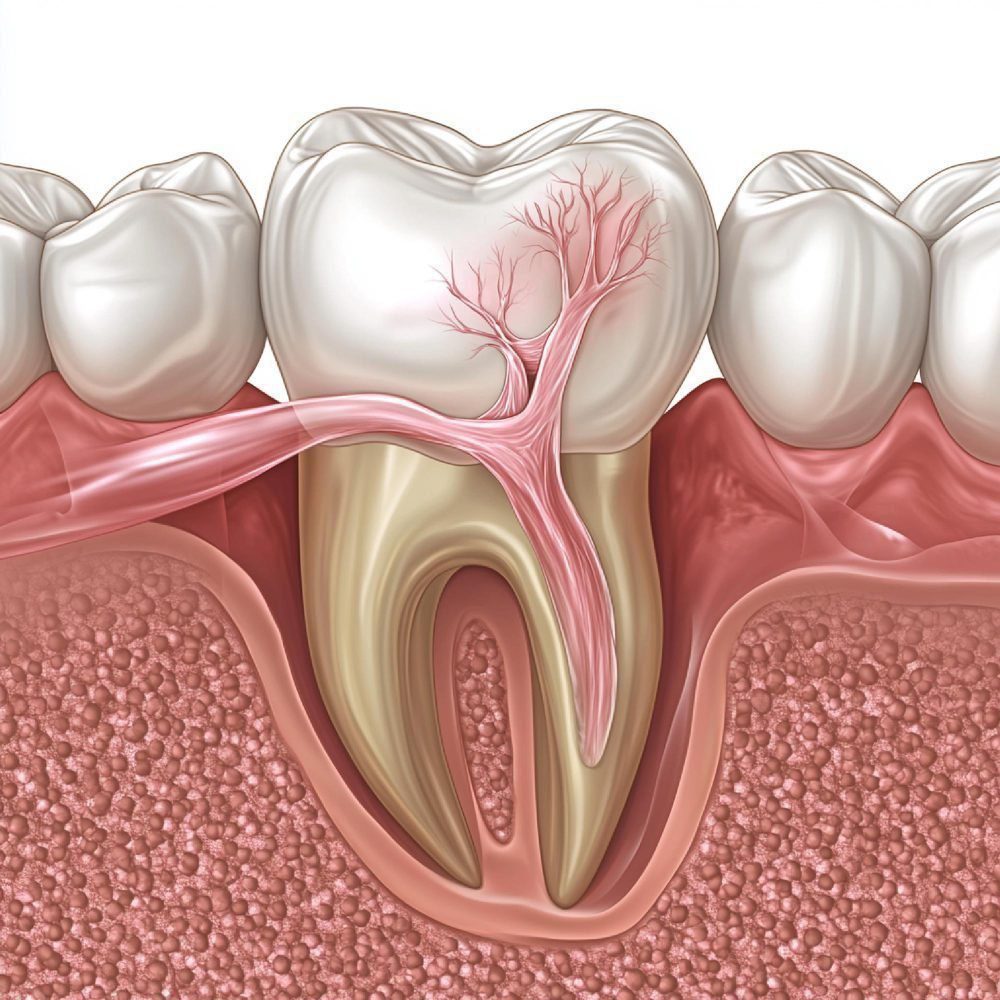

علاج جذور الأسنان في تركيا

أفضل عيادة لعلاج جذور الأسنان في تركيا – إسطنبول

علاج إصابات الأسنان الرضّية في تركيا

استئصال ذروة الجذر | علاج جذور جراحي

علاج خراج الأسنان في تركيا